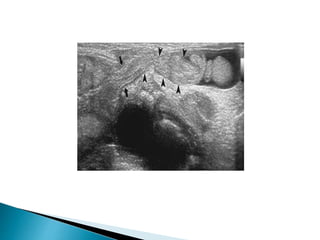

 On ultrasound the epididymis shows swelling,

 Diffuse or patchy reduction in echogenicity,

 Doppler ultrasound demonstrates

hypervascularity.

 A heterogeneous pattern of predominant

increase in echogenicity is more frequently

associated with chronic epididymitis.

 Often an associated hydrocele

 Edematous thickening of the overlying skin

 There may be coexisting orchitis